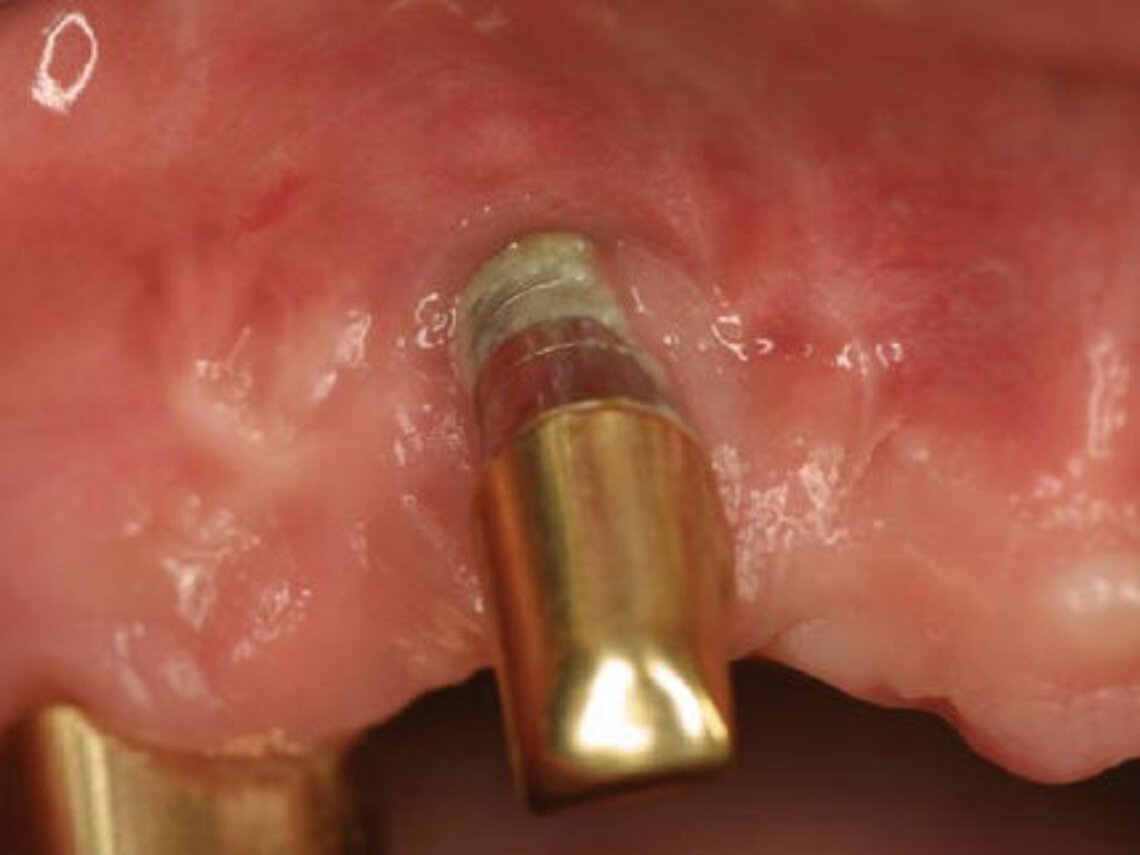

Peri-implant mucositis can be defined as an inflammatory lesion of the soft tissues (mucosa) surrounding the dental implant. Peri-implantitis is an inflammatory lesion of the mucosa affecting the supporting bone (crestal bone) with crestal bone loss and loss of osseointegration. Derks et al. report a prevalence of 43% for peri-implant mucositis and Jepsen et al. estimate that the prevalence of peri-implantitis could reach 22% (Figs. 1, 2).2,3 Peri-implantitis is usually accompanied by crestal bone loss (Fig. 3) and soft tissue changes in the peri-implant sulcus, which can be diagnosed by an increase in bleeding on probing (BOP) more than 5mm over previous examinations and/or suppuration8 (Fig. 4). Also excess of residual cement might contribute to crestal bone loss (Fig. 5).7